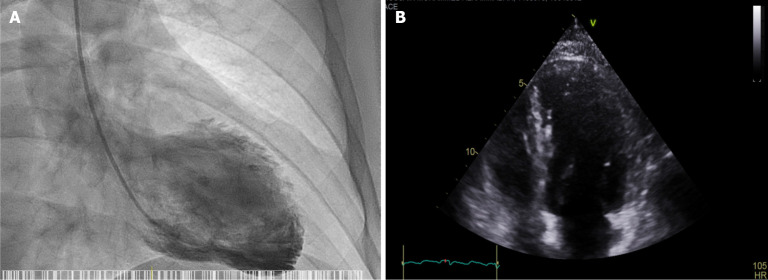

Abstract Image